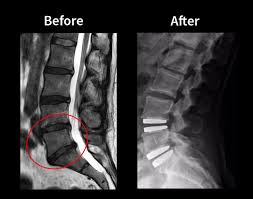

Spine surgery can fail if there is recurrence of slip disc even after disc removal surgery. This can occur either at the same level or some other level. Sometimes, spine surgery can fail due to failure to use spinal implants at the time of first surgery. Rarely, spine surgery can fail if the attempted union between the bones at the time of first surgery fails to materialize resulting in nonunion or implant failure. Another reason for failure of spine surgery can be progression of the degeneration in the spine to levels above and below the previously operated level.

Very commonly, we get patients with a failed previous spine surgery performed in their home country. We routinely perform revision surgery on such cases and ensure that their spine problem is solved and their problems are taken care of. To ensure maximum success in such complex cases we use new technology namely Carm, Pedicle screw instrumentation, High Speed Burr, Microscope, Navigation and Neuromonitoring to make even revision spine surgery highly successful. We have a lot of experience in dealing with such revision spine surgery cases and we can ensure successful outcomes even in these complex cases.

The Success rate of revision spine surgery in the hands of our expert spine surgeons at the best hospitals in India is about 95%. Approximate cost of revision spine surgery at the best hospitals in India is about 7000 to 12000 USD.